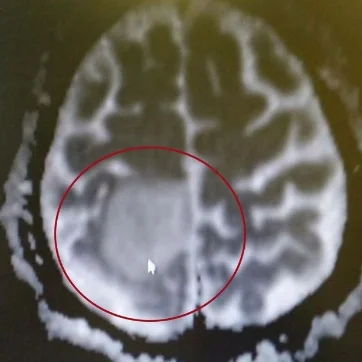

The tumour above Bens brain

Numerous tests and scans again followed, ultimately revealing a cancerous Brain Tumour, diffuse oligodendroglyoma , a cancer present throughout the brain but with an obvious growth at the top of his head.

Ben, mum, dad,brother Dan and family had their two weeks in Florida in October 2015. It was obvious however that Ben was not at his best. On return to the Uk further tests were undertaken revealing a new tumour site which appeared to be more aggressive. This was deep in the frontal lobe of Bens brain, the area responsible for emotions control and tact!!! Another biopsy another scar and the tissue results came back as similar to the first cancer, low grade. Huge relief.